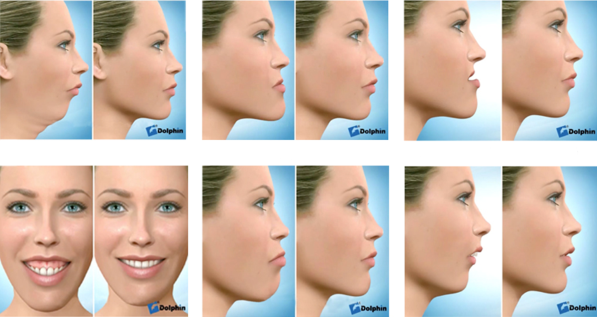

CIRUGÍA ORTOGNÁTICA

El tratamiento combinado de ortodoncia y cirugía ortognática permite tratar, ya sea por motivos funcionales o estéticos, aquellos casos en los que hay problemas de armonía facial en pacientes que ya han terminado su crecimiento, o en aquellos que exista una gran discrepancia entre sus huesos insalvable con ortopedia.

Las deformidades faciales se producen en los casos en que ha habido un exceso o falta de crecimiento del hueso que forma la cara, provocando un crecimiento anormal de este. Esta alteración tiene lugar durante la etapa del crecimiento, llegando a su estabilidad en la edad adulta. Cualquier hueso facial puede verse afectado por esta alteración (nariz, pómulos, mentón, mandíbula, etc.), dando lugar a una falta de armonía funcional y estética en el rostro.

Muchos pacientes que necesitan este tipo de tratamiento refieren dolores articulares, bruxismo, cefaleas y migrañas, ya que aunque la afectación estética sea notable, lo es más la afectación funcional. Puedes pensar que tú ya estás acostumbrado a padecer ciertos dolores y a comer con “tus dientes”, pero eso no quiere decir que no puedas mejorar, ven y pídenos opinión sobre tu caso!